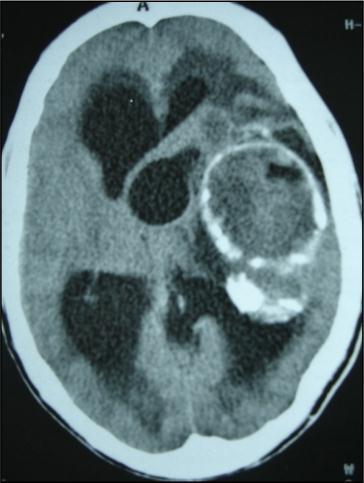

A 27 years-old male patient was admitted with 1 month history of headache, fever, short term memory lack, aphasia, right hemiparesis and seizures. He had liver hydatid cysts excised 8 years before and was treated with adjuvant medication (albendazole). The neurological examination revealed right central third cranial nerve palsy and hemi paresis, with Babinski sign positive, aphasia and papilledema on ocular fundus. The Glasgow Coma Scale was evaluated to 10/15 (E:3; V:1; M:6). A brain CT scan showed a large left temporoparietal intracerebral multiple and calcified hydatid cysts, important mass effect with midline shift about 7 mm following by an obstructive hydrocephalus (Figure 1). Other cysts were found in thalamic region (Figure 2). The Thoraco-abdominal CT scan showed multiple intra peritoneal hydatid cysts (Figure 3). A left temporo parietal craniotomy was performed in emergency. After corticectomy, using Arana-Iniguez technique, the appearance of the capsule suggested infected hydatid cysts with a purulent material which was aspirated. Numerous hydatid cysts were lifted away and several daughter vesicles were carefully removed without rupture (Figure 4). Macroscopically, the abscess wall appeared to be thick, calcified and tightly attached to lateral ventricular, so it could not be removed. The deep cyst overlying the third ventricle was left.in place. Microscopic examination demonstrated live scoleces, protoscoleces and multiple hooks. These findings are consistent with hydatid cyst (granulosis ecchinococcus) (Figure 5). Bacteriology examination found several white blood cells in the pus (neutrophilia) and infection by streptococcus pneumonia. This was consistent with infection. After surgery, the patient had medication (albendazole, specific antibiotherapy and phenobarbital). The inflammation assessment in the blood showed leukocytosis, a high C-reactive protein rate and increased erythrocyte sedimentation rate. Post operative CT scan was performed and showed the residual calcified capsule and decreased ventricular size (Figure 6). Clinical improvement was achieved after treatment. One month after the initial diagnosis, CT scan of the brain showed no recurrence and a physical examination revealed a neurologically intact, fully functional patient and eyes fundus normal. He was discharged and went to abdominal surgery two months later with complete intra abdominal cysts removal. Albendazole treatment was continuing for six months and radiological exploration was performed by brain MRI with spectroscopy at three and six month later. This showed that infection had resolved and the deep cyst overlying the third ventricle is less spherical (Figure 7, Figure 8). Four years later, the outcome was good.

Figure 6.post operative CT scan showing the residual capsule.